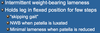

History Typical of _____ Cranial Cruciate Ligament Disease:

Significant Hind Limb Lameness that is Aggravated by Activity or After Rest

Intermittent/Progressive Hind Limb Lameness- Slow Degeneration of Ligament leads to Degenerative Joint Disease

Difficulty Rising

“Bunny Hopping”- Bilateral

Chronic

*Highly Variable Presentation- Early in the Disease, signs may be Mild or Episodic with lameness seeming to Resolve between Bouts

*Envision the Diseased Ligament as a Weakened, Braided Fraying Rope- Individual Fibers give way Progressively